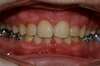

Intra Orale Face